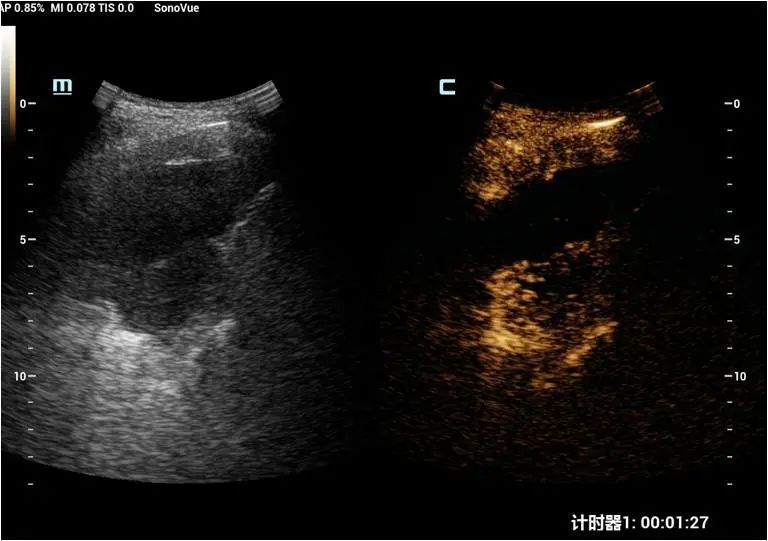

超声医学科接诊该患者后先行超声检查+超声造影评估,于右侧背部肋间检查发现患者右肺下叶低回声肿块,大小约53×32mm,可见斑片状强回声及无回声,CDFI:见血流信号。超声造影见该团块早于周围组织灌注,灌注不均匀,灌注峰值高于周围组织,内见少许无灌注区。